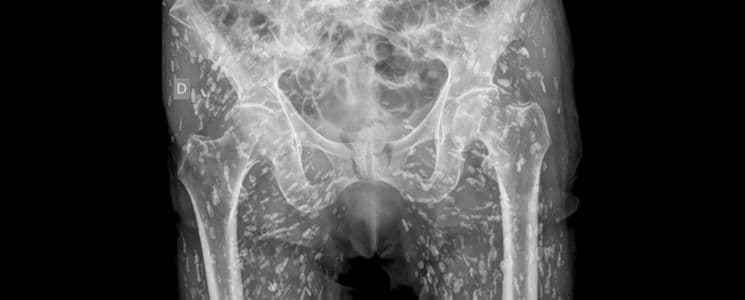

Di dalam tubuh seorang pasien di Florida, Amerika Serikat (AS), ditemukan ratusan larva cacing pita. Kasus ini diungkap oleh dr Sam Ghali, yang menyebut pasien tersebut sebelumnya mengonsumsi daging babi setengah matang yang mengandung larva cacing pita.

“Nasib nahas harus dialami pasien ini. Larva cacing menetas dalam tubuhnya, menyebar ke jaringan, dan bahkan membentuk kista di tubuhnya,” kata dr. Sam Ghali, dilansir dari detikhealth, pada Minggu (26/1/25).

Lanjutnya, infeksi cacing pita atau dikenal sebagai sistiserkosis sangat berbahaya. Larva cacing dapat membentuk kista di berbagai jaringan tubuh, seperti otot, otak, hingga mata.

“Sistiserkosis bisa menyebabkan berbagai gejala, seperti sakit kepala, kejang, dan kebingungan jika menyerang otak. Bila mengenai mata, infeksi ini bahkan bisa menyebabkan kebutaan,” ungkap Aru.